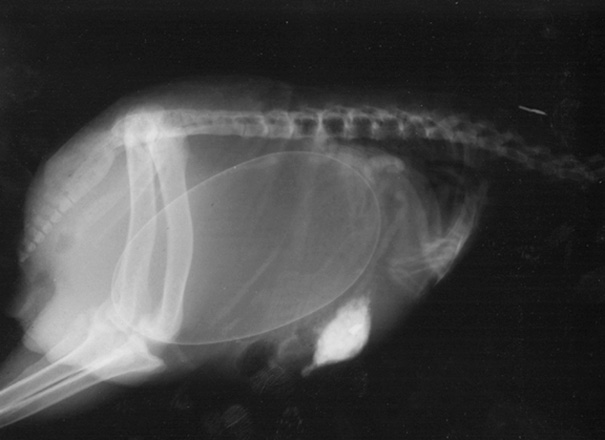

Unikāli rentgena attēli ar dzīvniekiem gaidībās

Bieži negadās publiski redzēt dzīvnieku rentgena uzņēmumus. Turklāt šie rentgena uzņēmumi ir veikti dzīvniekiem, kuri ir mazuļu gaidībās. Tagad ikvienam ir iespēja ielūkoties, kā dzīvnieku mazuļi attīstās savu mammu vēderos.